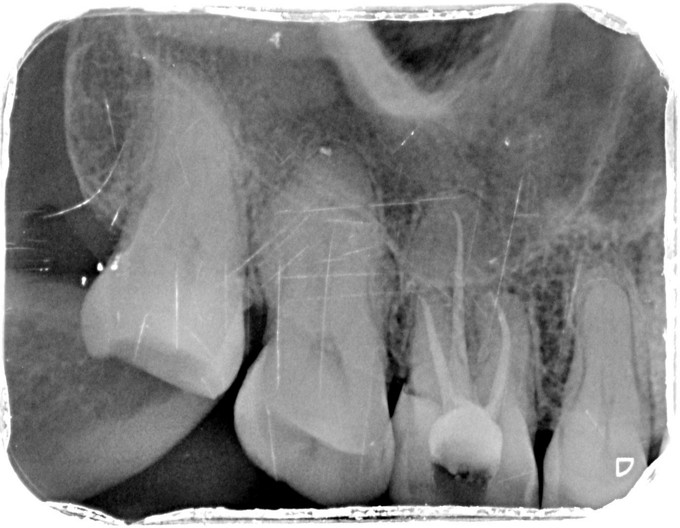

临床检查:16牙合面充填物完好,探疼(+),冷(++),叩(-),松动度(-),无窦道,牙周正常. 辅助检查:X线示16龋坏累积髓腔,根尖周牙周膜略增宽。

诊断:16继发龋伴牙髓炎 治疗:经患者知情同意后,16局麻去除原有充填物降牙合,开髓拔髓寻找根管口,建立直线通路,扩通根管,确定工作长度。S3/EDTA凝胶镍钛器械,低浓度次氯酸钠冲洗根管,预备至35/04,氢氧化钙诊间封药,一周后复诊,试主尖X线示恰充,试干根管,导AH-PLUS糊剂,VDW热压胶垂直加压根充,术后见根管恰充,暂封观察嵌体修复。